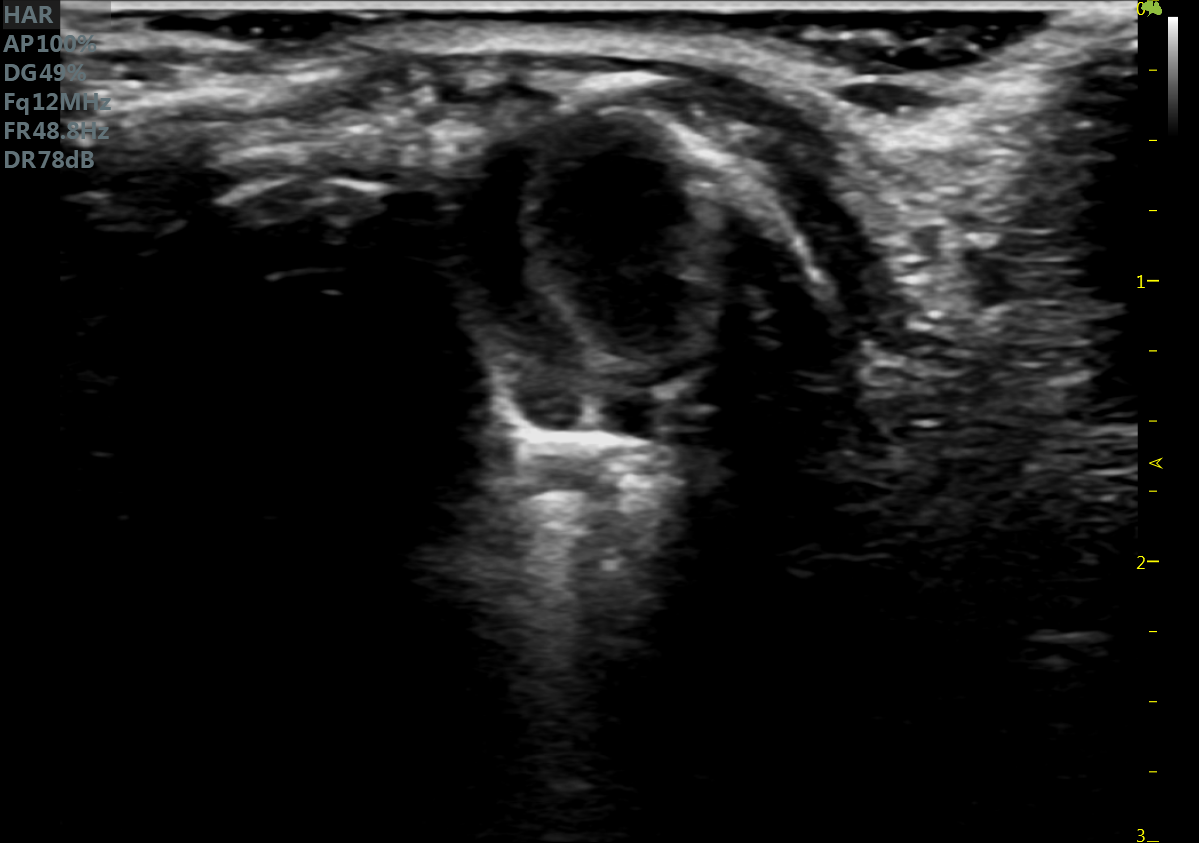

小鼠长轴M型 小鼠短轴M型

小鼠长轴B型 小鼠短轴B型